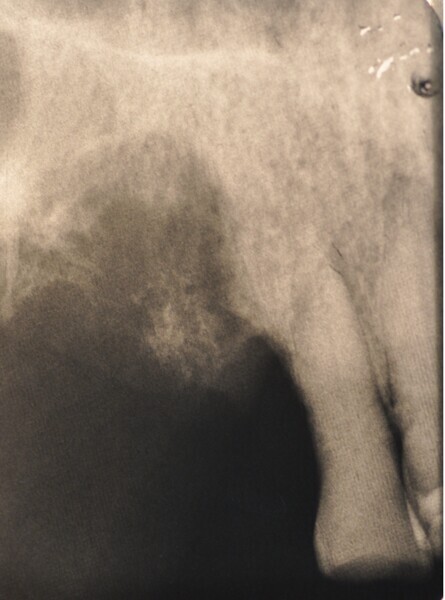

Osteonekroza występująca po zastosowaniu bisfosfonianów